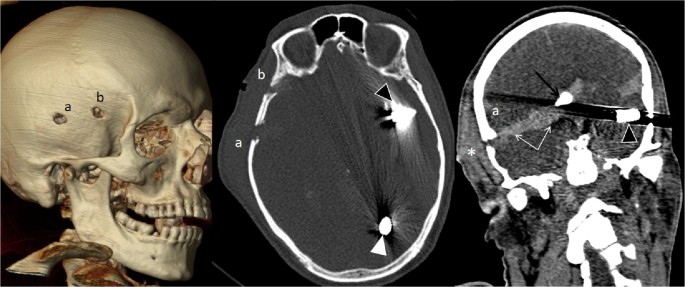

일반적인 권총 탄환, 예를 들어 9mm 탄환은 두개골을 관통하고 굴러가서 멈추지 않는 한 그대로 관통합니다. 이는 거리에 따라 달라지는데, 속도가 멀어질수록 떨어집니다.

5.56과 같은 소총 탄환은 두개골을 관통한 후 폭발하거나 파편화되어 최대의 파괴를 초래합니다. 거리에 따라 머리가 폭발할 수도 있습니다. 이 총알은 이를 위해 설계되었습니다. 이것이 의사들이 AR로 총에 맞은 학교 총격 사건 피해자를 치료해야 하는 상처를 두려워하는 이유입니다. 총알이 들어가 뼈에 맞고 폭발하여 주변 조직에 온갖 손상을 입힙니다.